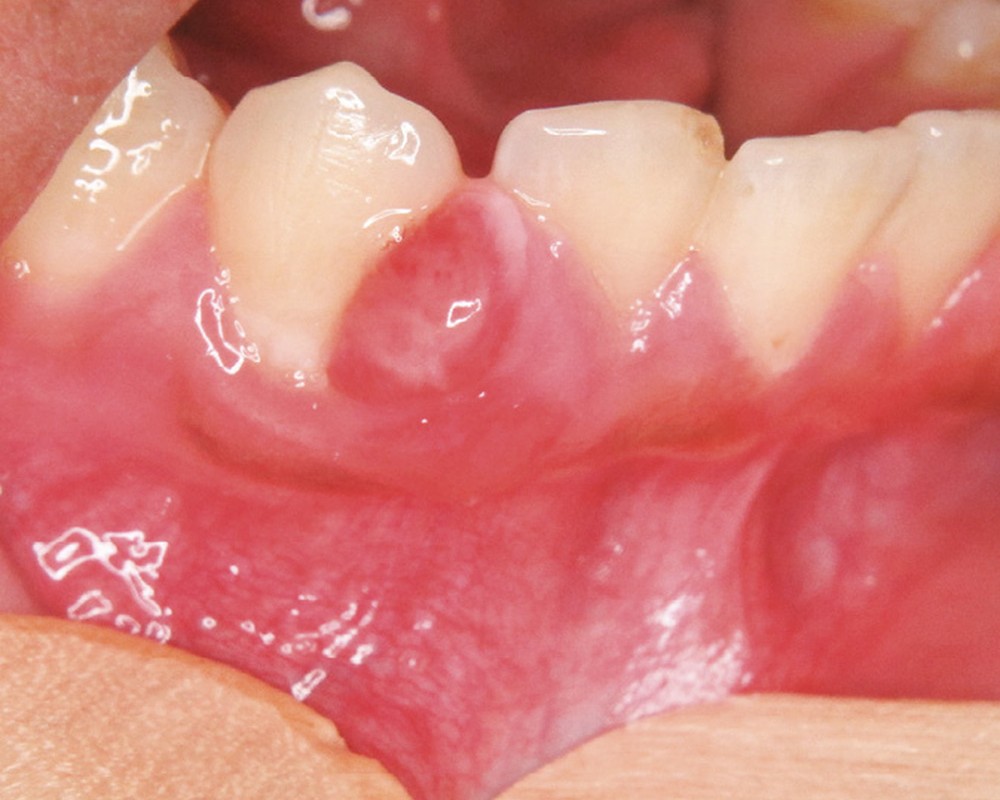

6c. Epulis : granulome non spécifique réactionnel de cause locale.